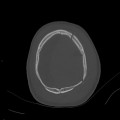

[TDM] Crâne -/+

SCANNER CÉRÉBRAL

INDICATION

TECHNIQUE

Scanner cérébral sans puis avec injection de produit de contraste iodé

DLP :………………. mGy.cm

Pas de complication au décours immédiat

RESULTATS

Structures médianes en place

Pas d’anomalie de densité du parenchyme cérébral sus ou sous-tentoriel en contraste spontané

Absence de prise de contraste parenchymateuse ou péri-cérébrale suspecte

Structures veineuses perméables

Structures ventriculaires fines et symétriques

Pas de signe d’hémorragie intra ou extra-axiale

Citernes de la base libres

Pas d’anomalie de la charnière cervico-occipitale

Structures sinusiennes libres

Pas de lésion osseuse suspecte visualisée

CONCLUSION

Absence d’anomalie décelée

Iconographie mise à disposition sous forme de planche papier et conservée localement sur le PACS